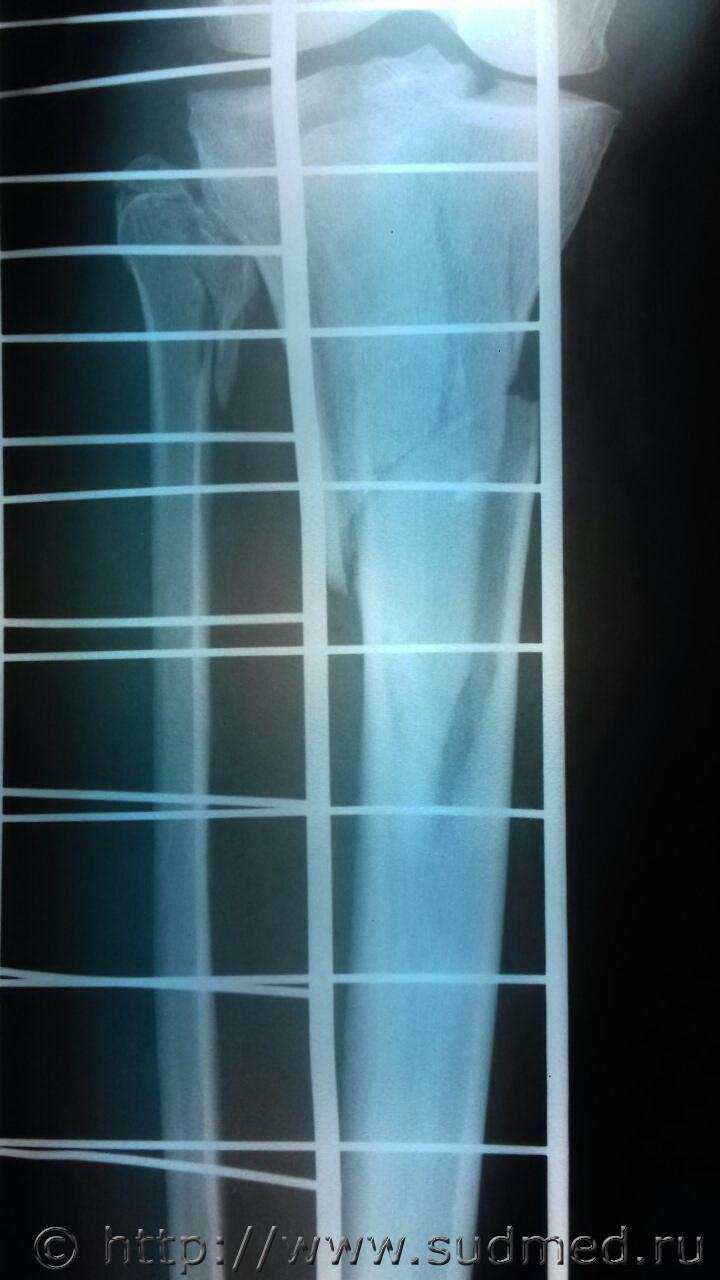

и снова рентгены живых лиц! обстоятельства: ДТП. Пешеход. Нужно определить направление травмирующего воздействия. На коже ничего врачи не зафиксировали

Винт. Кручение проксимального отломка кнаружи, дистального - кнутри.

Винтообразный (спиралевидный) перелом.

Здесь не чистый винт. Здесь винт с изгибом внутрь. Верхний кончик дистального отломка отсутствует (где-то валяется видимо, не видно), продольный перелом проксимального отломка с разрушением суставной поверхности. Да и похоже на подвывих в коленном суставе - суставная щель по высоте разная.

Перелом головки малоберцовой кости виден. Она от чистого кручения по оси большеберцовой кости не ломается.

Благодарю за внимание всех! голень правая. Сомнения потому и возникли, что винт странный через суставную поверхность проходит. А если это сочетание удара и вращения?????